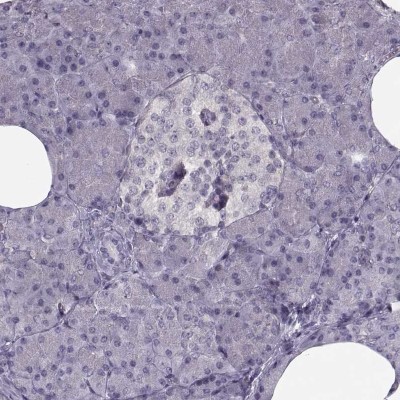

- Experimental details

- Immunohistochemistry-Paraffin: LUZP2 Antibody [NBP2-14564] - Staining of human pancreas shows low expression as expected.